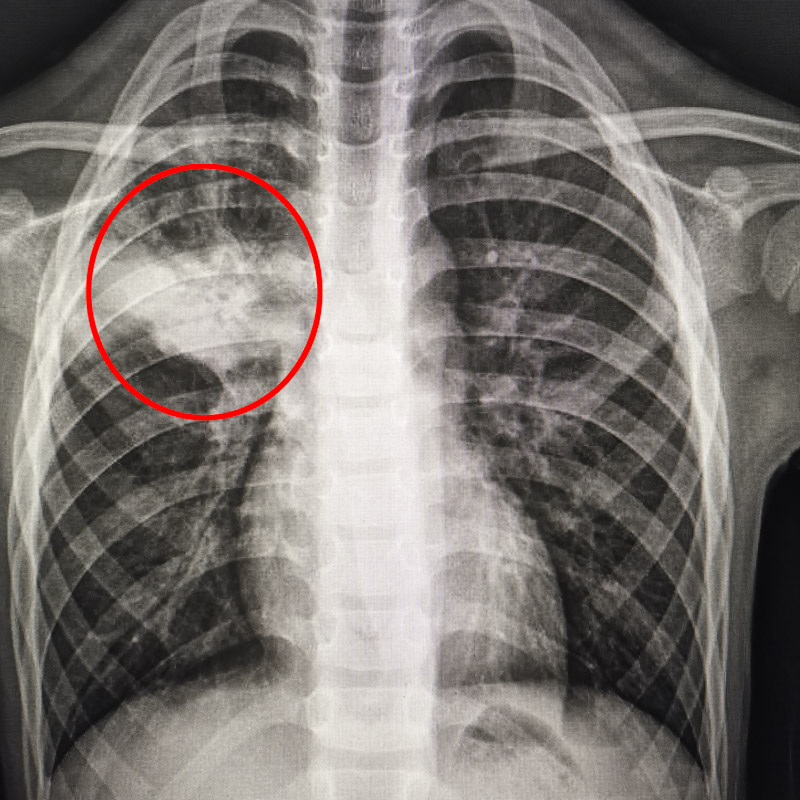

家長(zhǎng)焦急地帶孩子前往柳州市人民醫(yī)院兒科就診。小萱的胸片報(bào)告顯示,她的右上肺出現(xiàn)一大片感染灶。家長(zhǎng)很驚訝,從發(fā)病到檢查出肺部大片感染灶,病程才5天,病情進(jìn)展太快了。